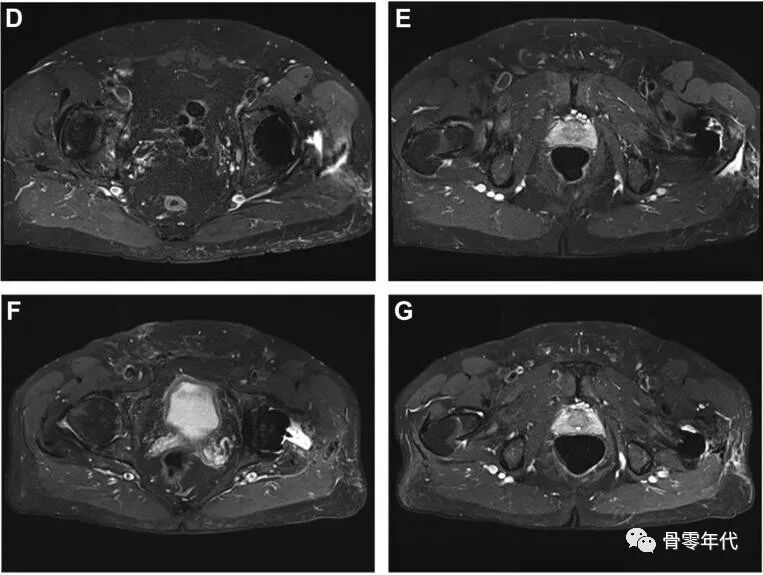

(A-C)术前X光显示左侧股骨近端骨量减少,翻修时预先放置的模块化骨干接合股骨柄用于假体周围骨折的治疗。(D和E)在外展肌重建前进行的MRI图像显示臀中肌和小肌脂肪萎缩,股骨肌腱附着处改变。(F和G)外展肌重建18个月后的部分MRI图像显示臀中肌附着完整,臀小肌部分连续。患者报告的外展肌重建术23个月的结果包括:静息疼痛,1/10;行走疼痛,3/10;Harris髋关节评分,61;牛津髋关节评分,22。患者报告中度跛行,仅需长时间步行时需要拐杖。